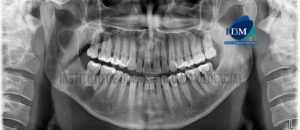

Paciente masculino de 48 años acude al Instituto de Diagnóstico Maxilofacial para evaluación postquirúrgico de lesión benigna de origen odontogénico (Amelobalstoma). A la evaluación de